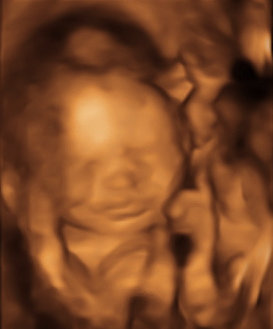

Our excitement and anticipation for Luna led us to document every stage she goes through. At 12 weeks you can see our angel was almost the size of a lime... Then, at 20 weeks, she grew into a good-sized fig. Upon arriving, our Luna will hopefully be the fully-grown Melon she’s meant to be! You can check out her journey here. We want everyone to be part of the amazing ride we are going through!